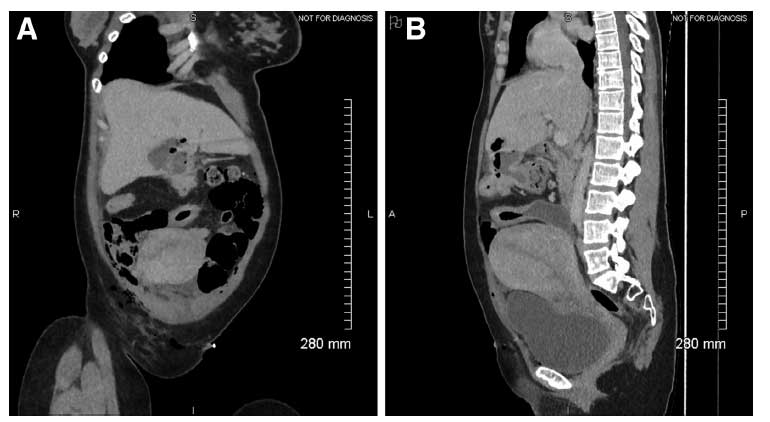

QUIZ: Uma rara complicação relacionada à gravidez da doença de Crohn: diagnóstico e tratamento